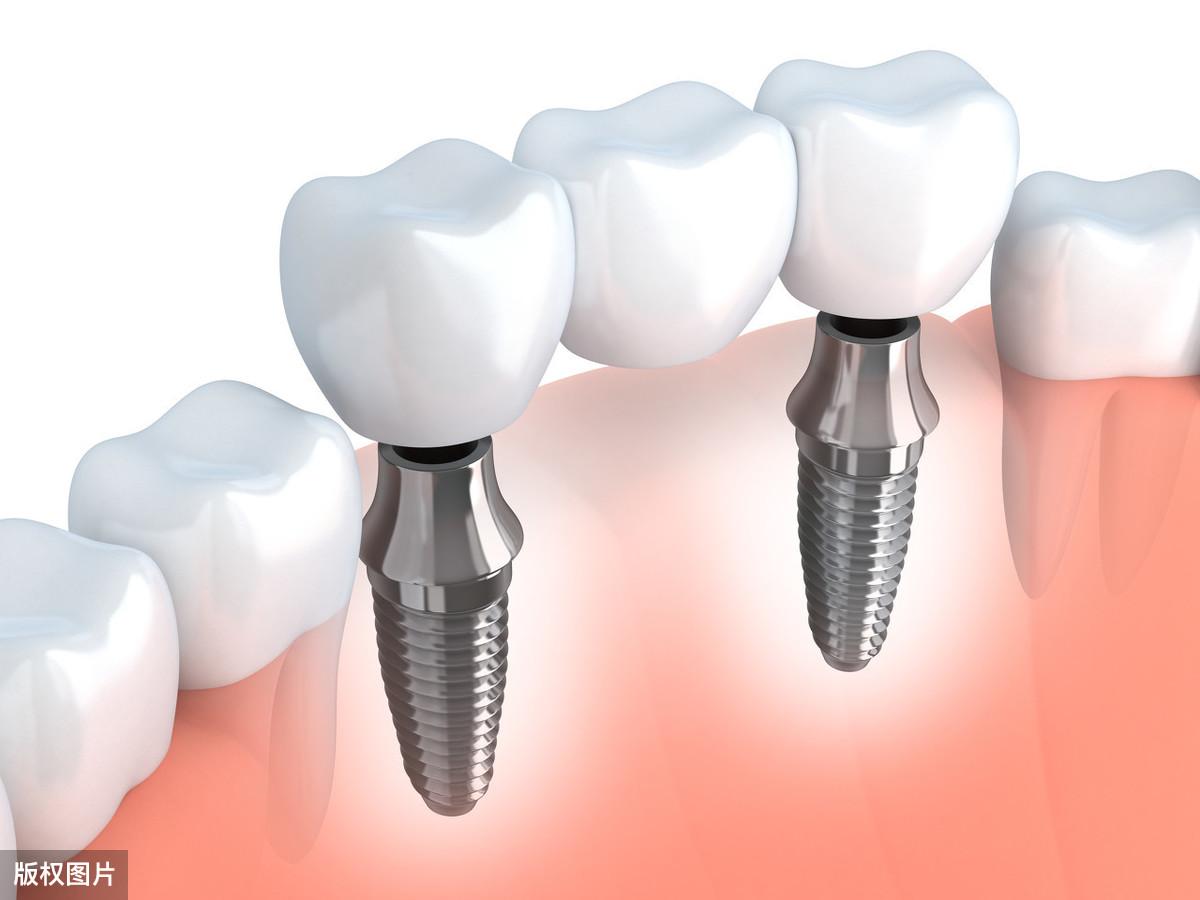

種植牙手術(shù),是門診的常規(guī)小手術(shù),它是將生物材料制成的一種人工牙根(種植體)植入到人體的頜骨內(nèi),然后在人工牙根上做上牙冠,從而恢復(fù)口腔的咀嚼功能及美觀。

種植體---基臺---牙冠